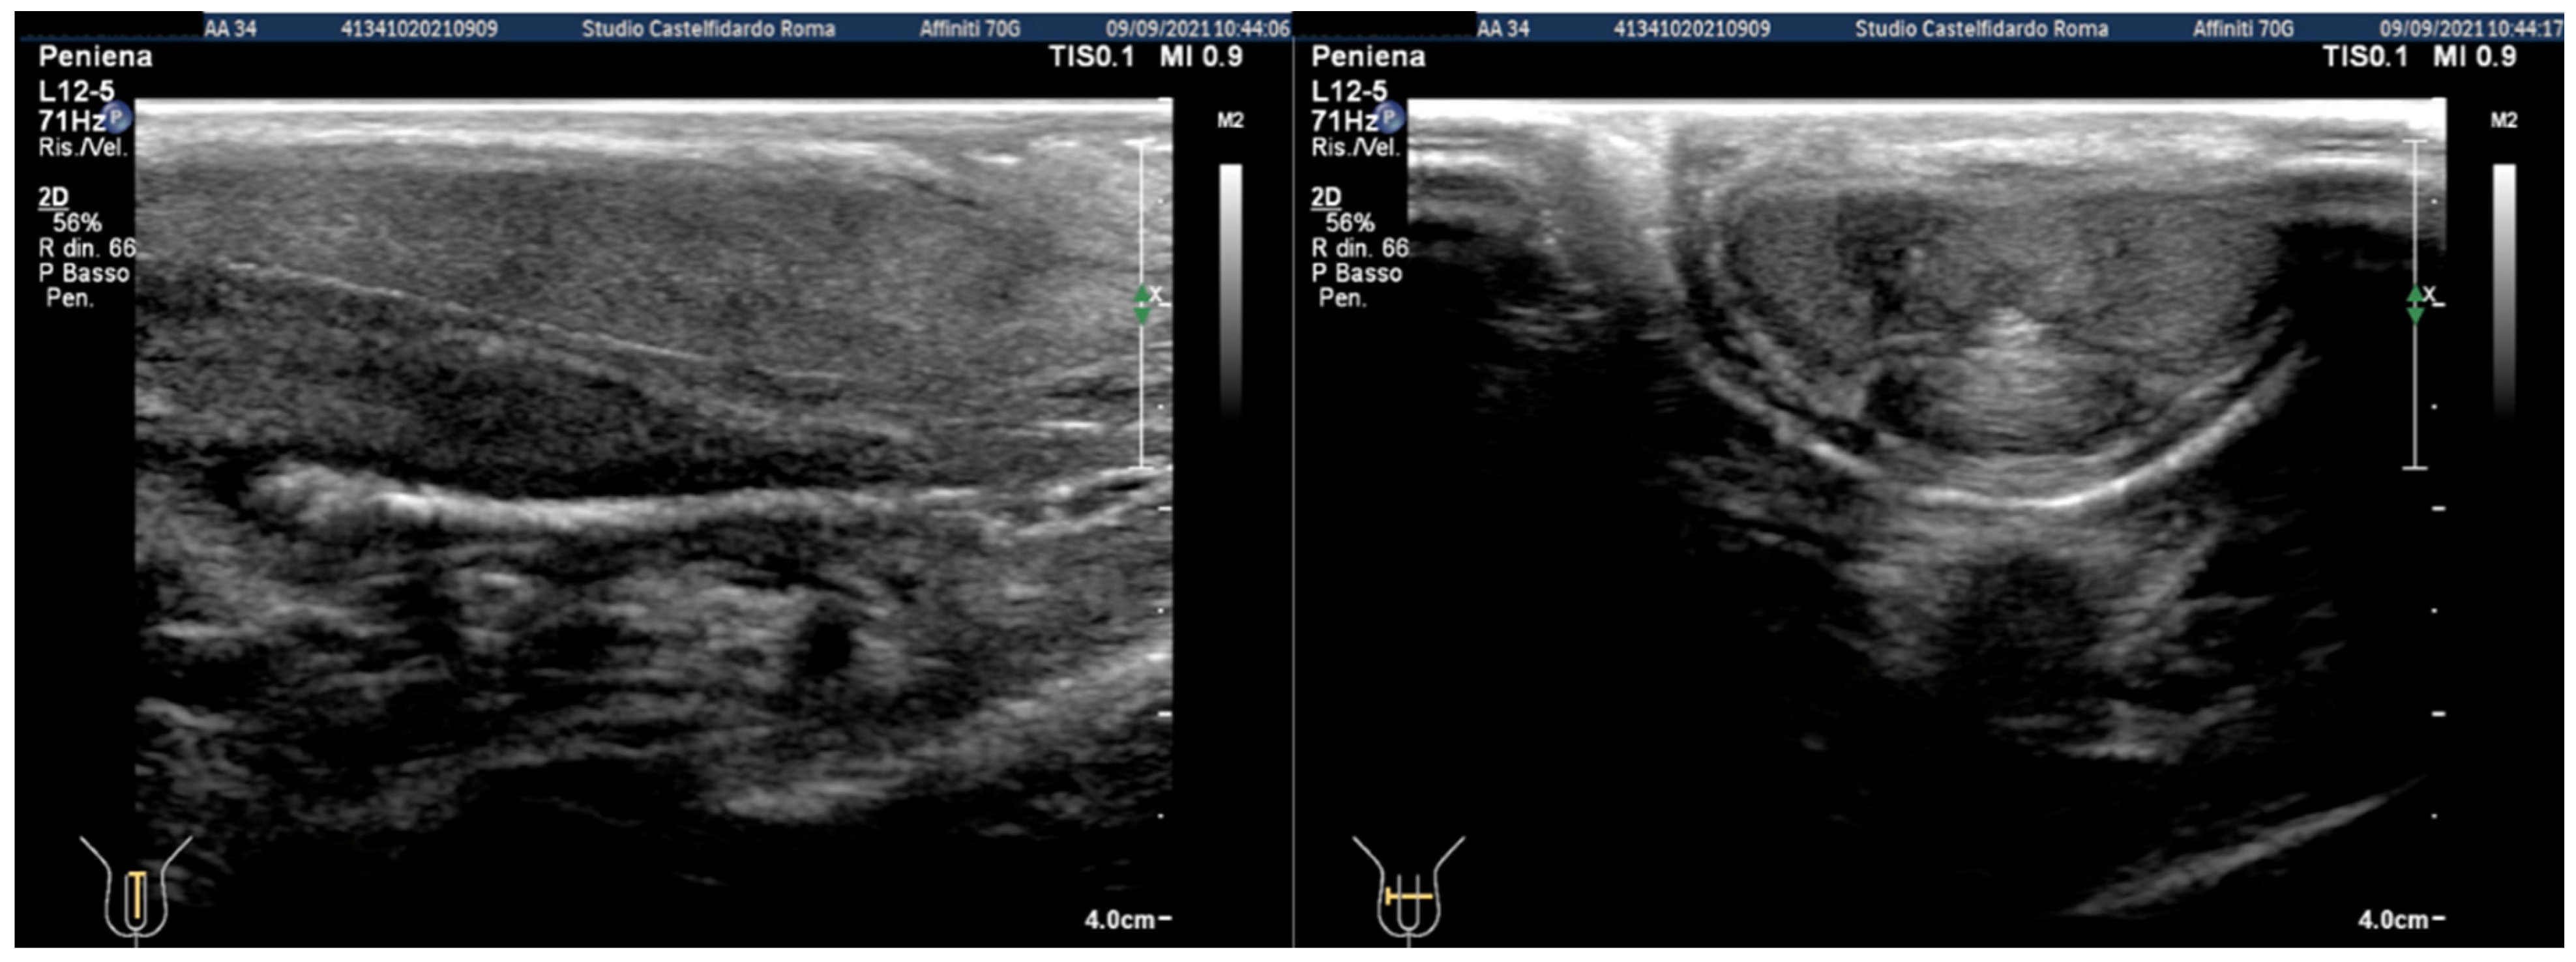

| 3 | 30 years | Left varicocele | Proximal third | (A) 12.2 × 11.2 × 2.81 mm volume = 203 mm3 (B) No plaque detected | (A) No penile deformation (B) No penile deformation | VAS score = 5 Pain disappeared after 4 months | 26 > 26 | 4 months | Orally: propolis 600 mg + bilberry 160 mg + silymarin 400 mg + ginkgo biloba 250 mg + vitamin E 800 IU/daily for 4 months + topically: diclofenac gel 4%/2× daily for 4 months Note: Penile injections not needed |